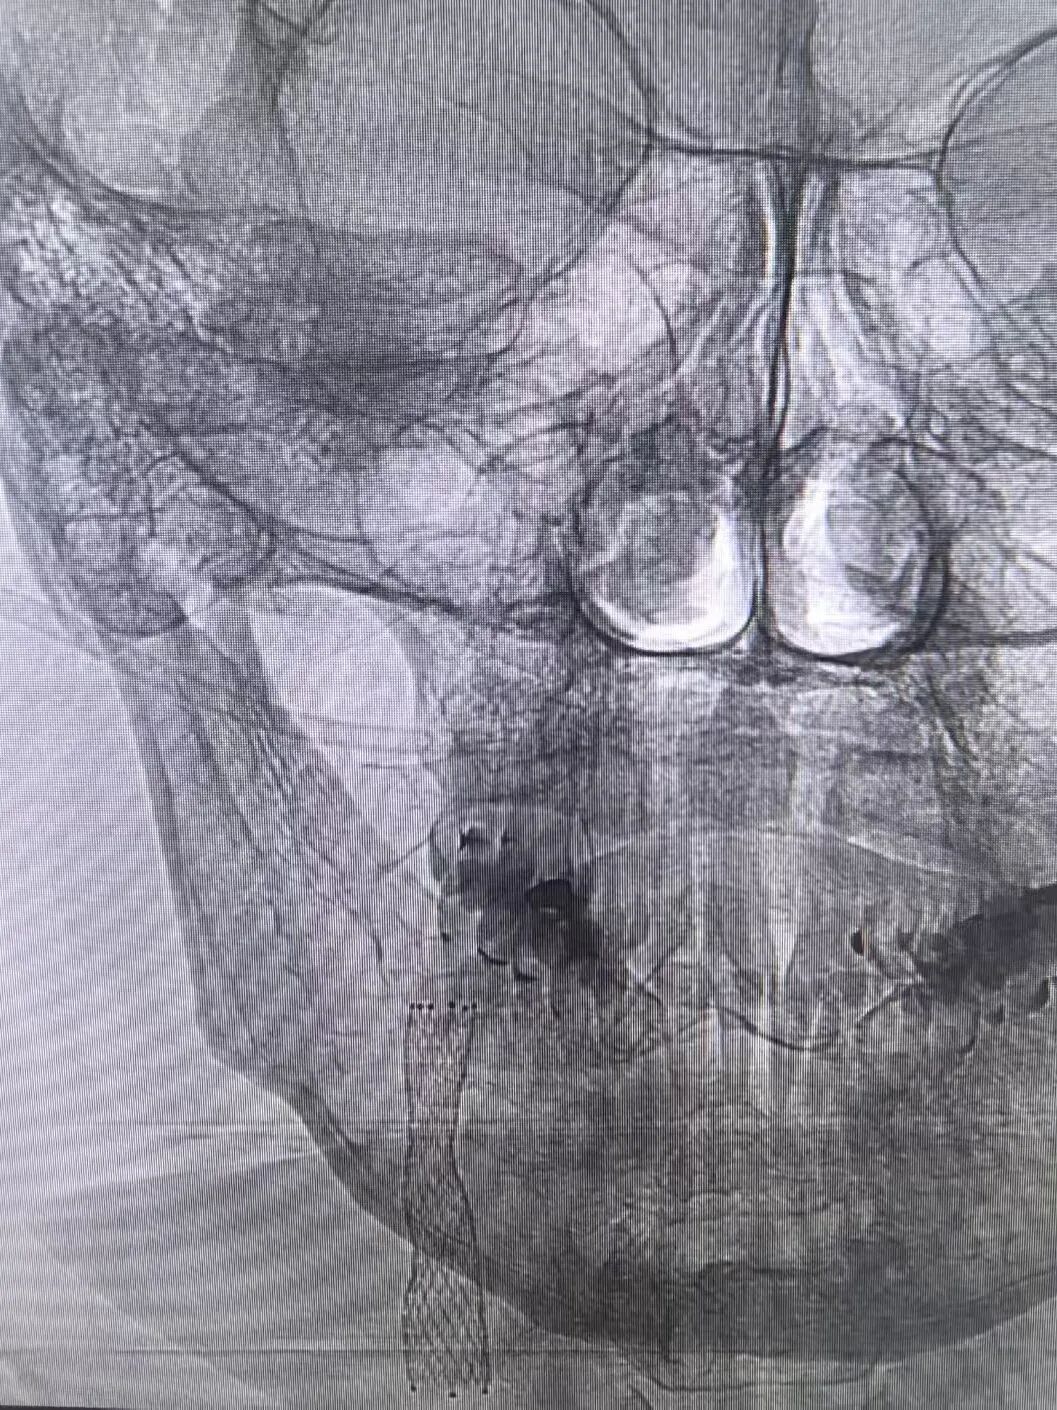

DSA显示罗先生颈动脉闭塞

置入支架术后影像

心脏问题刚解决,脑部危机便接踵而至。医疗团队迅速为罗先生实施脑动脉造影,结果显示其右侧颈内动脉近段狭窄达99%。然而心脏术后需维持稍高血压保障心功能,颈动脉支架手术却要求严控血压以规避脑出血风险——两种治疗需求如同天平的两端,在罗先生体内形成了棘手的治疗矛盾。手术团队经过反复研讨、全面评估,与家属进行了充分沟通,决定暂缓脑部手术,给予患者充分的恢复时间,待身体条件达到最佳状态后,再实施颈动脉支架植入手术。

同时,王和平教授紧急到院,带领诊疗团队采用股动脉穿刺微创通路,在DSA引导下精准植入支架,40分钟内解除颈动脉闭塞,造影显示颈动脉血流恢复通畅,术后次日患者即可下床活动。